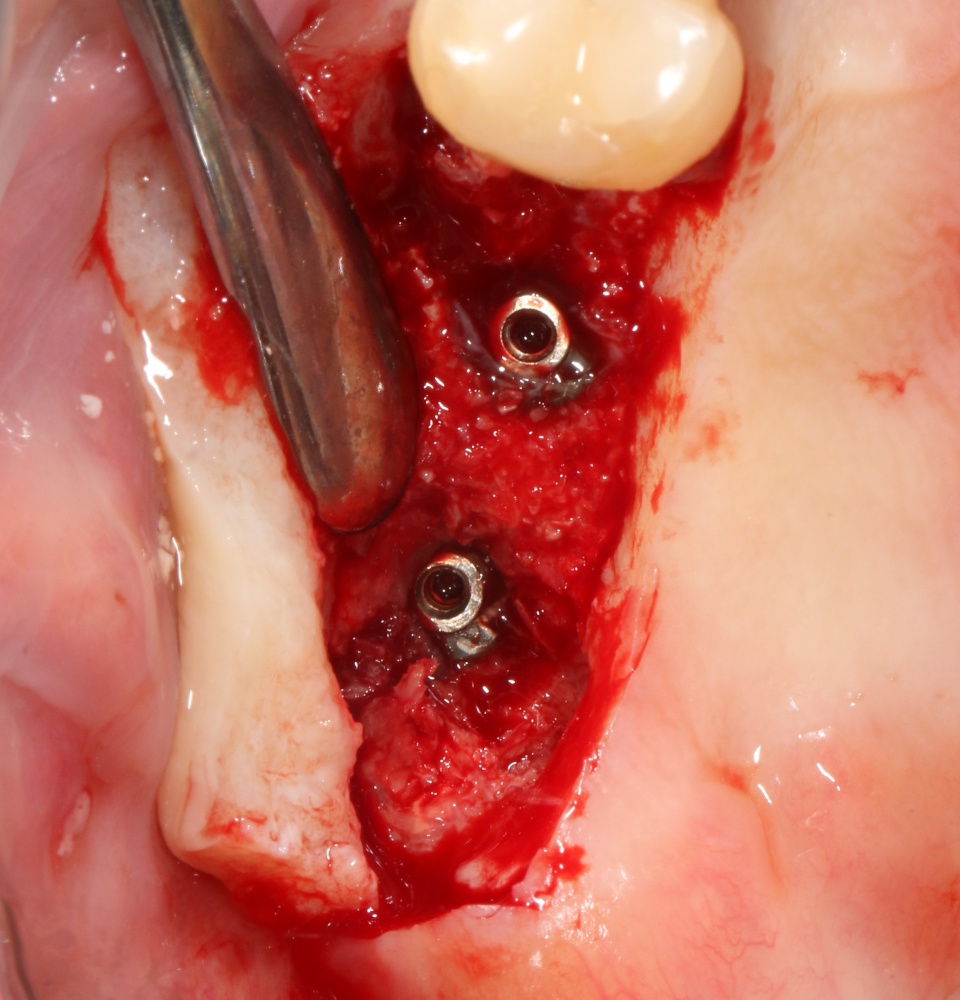

— обеспечивает достаточную первичную стабильность имплантатов, поэтому нередко применяется совместно с имплантацией.

Недостатки

— высокая травматичность в сравнении с другими методами остеопластики, и это, пожалуй, главный недостаток метода аутотрансплантации. Для того, чтобы кость пересадить — её нужно где-то взять, а для этого следует подобрать донорский участок, выделить костный фрагмент, подготовить его и т. д. По сути, забор аутотрансплантата может превратиться в еще одну операцию.

— значительная техническая сложность. Надо выбрать костный аутотрансплантат нужного размера, подготовить для него ложе, неподвижно зафиксировать и т. д. — и всё это, иногда, в очень тесных условиях. Также необходимым условиям успешного результата является точная подгонка костного блока под принимающее ложе (или наоборот) для обеспечения максимального контакта. А это непросто.

— необходимость специального оборудования. Правильно провести аутотрансплантацию, используя подручные и привычные инструменты, крайне сложно.